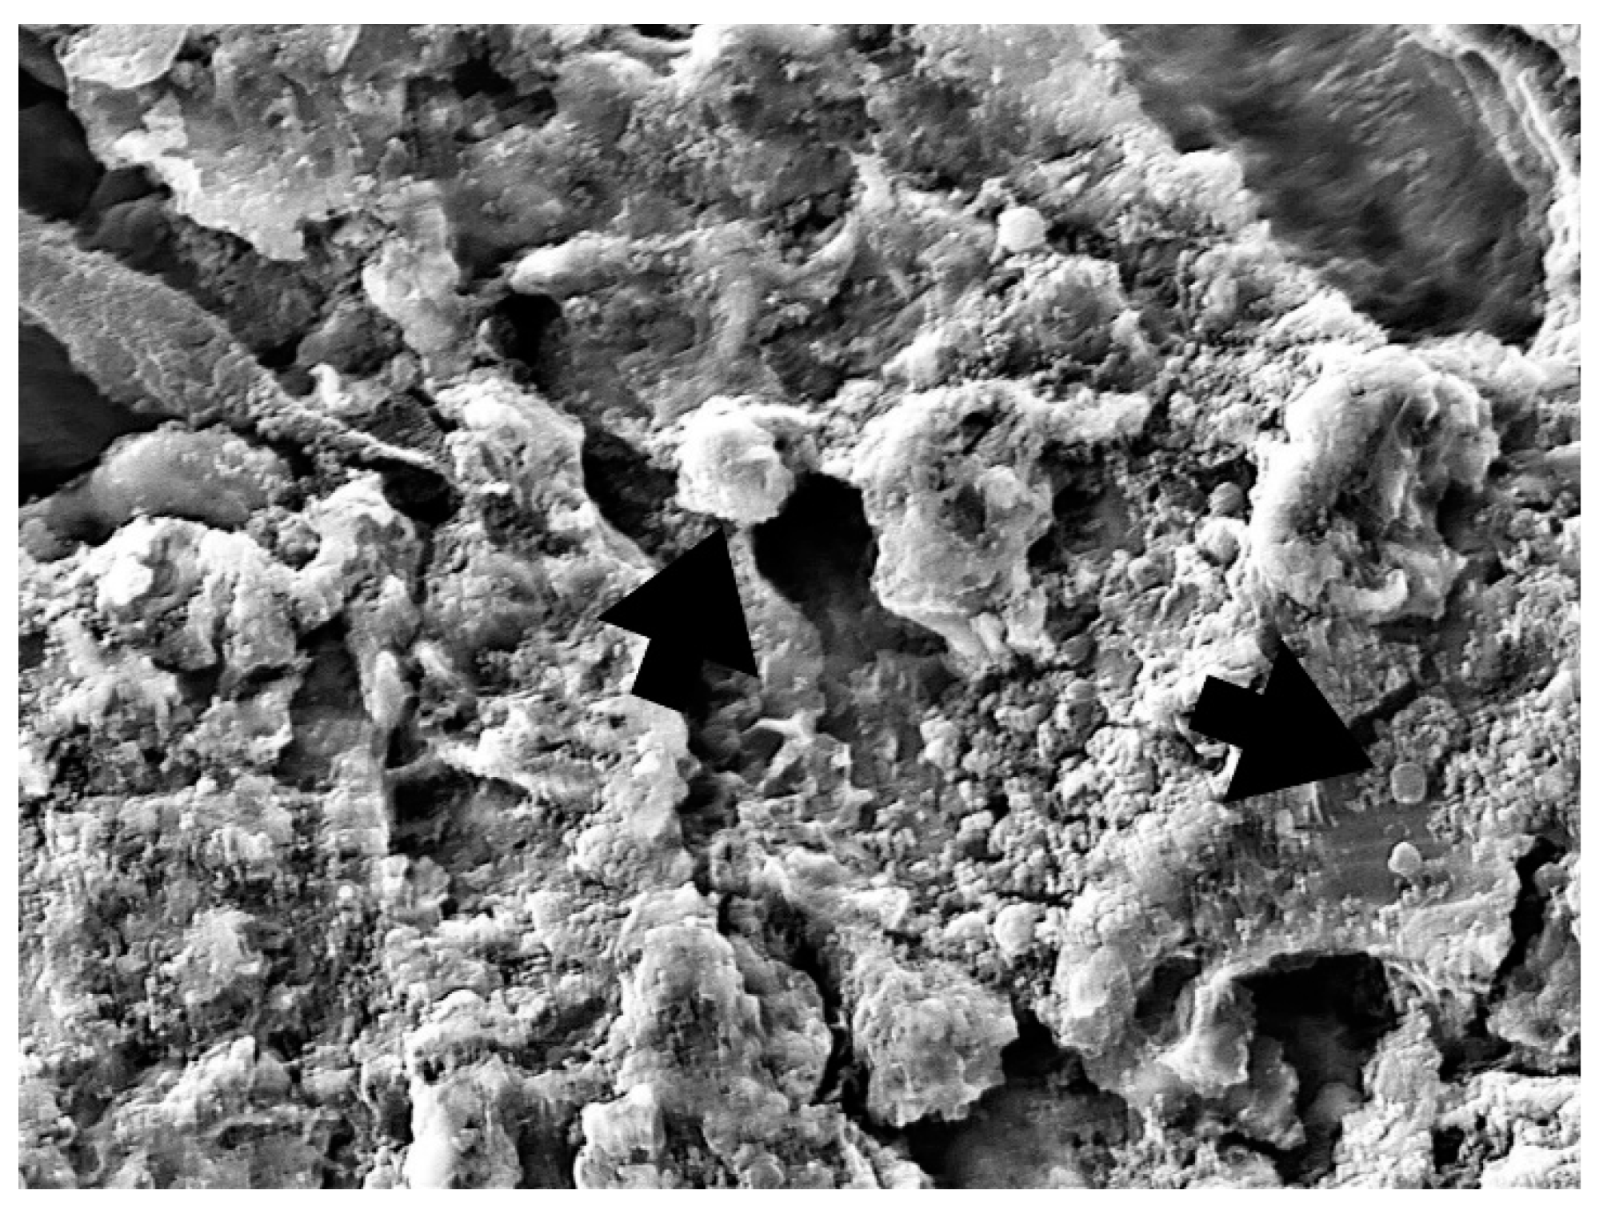

- Leelanarathiwat, K.; Katsuta, Y.; Katsuragi, H.; Watanabe, F. Antibacterial activity of blue high-power light-emitting diode-activated flavin mononucleotide against Staphylococcus aureus biofilm on a sandblasted and etched surface. Photodiagnosis Photodyn. Ther. 2020, 31, 101855. [Google Scholar] [CrossRef] [PubMed]